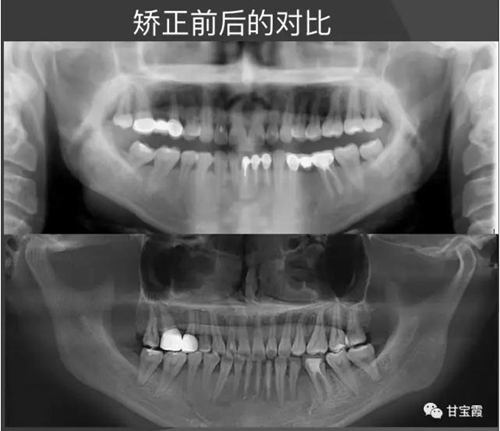

經(jīng)過28個月的矯正,大家可以看到原來的兩個缺牙間隙沒有了,舊的烤瓷牙換成了全瓷冠修復(fù)。下面的圖片是矯正前后的X線對比,

下圖是矯正前后的開口頜像的對比,患者朋友看到這么好的治療效果,很后悔幾年前做的烤瓷修復(fù),還白白的磨了好牙。